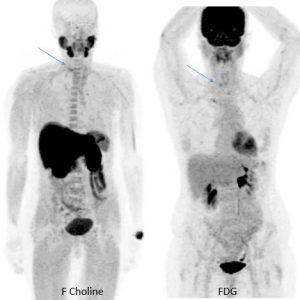

Une scintigraphie TEP FDG est réalisée et met en évidence une faivle activité métabolique en regard de la lésion lytique (SUV = 3.7).

Devant cette faible activité métabolique, l’exploration est complétée par un TEP FCholine…

Finalement le niveau de fixation du FDG et de la F choline est identique. La TEP F Choline ne révèle pas d’autres localisation.

Le myélogramme étant normal, la lésion de T1 étant isolée, il s’agit d’un plasmocyte solitaire.

L’ana path précise que seulement 2 mitoses par champs sont observées sur la biopsie, la faible agressivité cellulaire est concordante avec la faible activité métabolique.